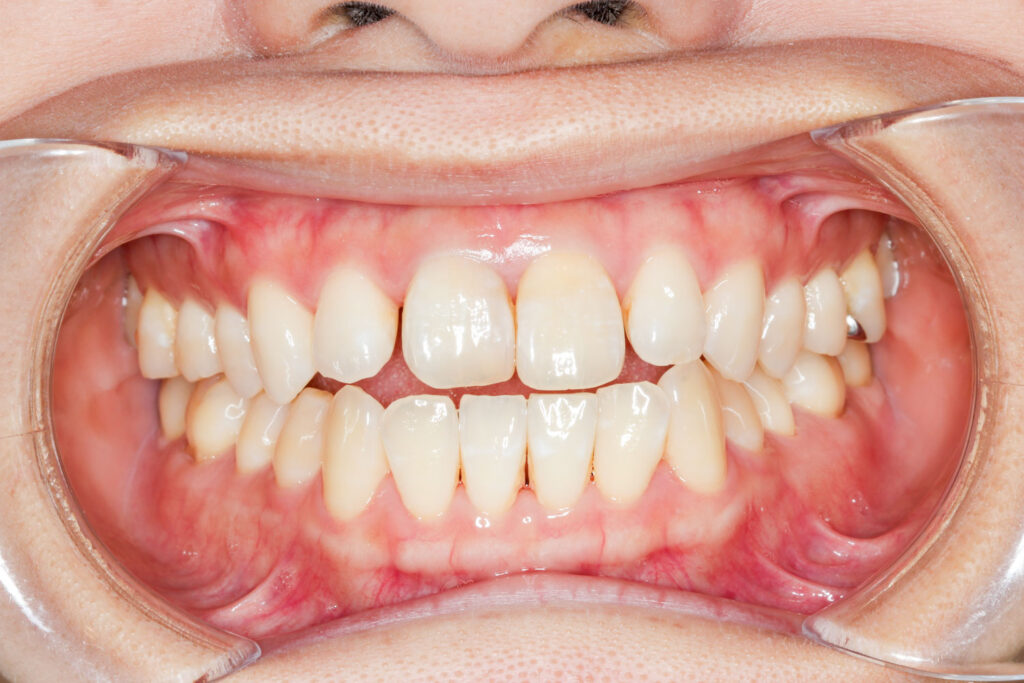

Before

After

年齢 10代

治療装置 上は裏側の矯正装置(ハーフリンガル)

治療内容 上下左右4本抜歯

治療期間 2年8か月

リスク 歯の移動に伴う痛み、歯肉退縮、歯根吸収、歯肉炎、虫歯

主訴 八重歯が気になる

症状 叢生(ガタガタ)

治療回数 33回程度

総額費用 125万円程度